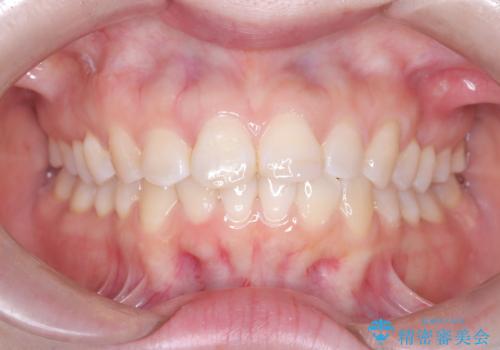

前歯の突出を防ぎながらガタつきを解消。上下左右4番抜歯による審美ワイヤー矯正

担当医 河口智英